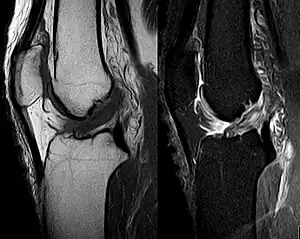

Medical imaging

Though clinical examination in experienced hands can be accurate, the diagnosis is usually confirmed by magnetic resonance imaging, which provides images of the soft tissues like ligaments and cartilage around the knee.[1] It may also permit visualization of other structures which may have been coincidentally involved, such as the menisci or collateral ligaments.[30] An x-ray may be performed in addition to evaluate whether one of the bones in the knee joint was broken during the injury.[9]

MRI is perhaps the most used technique for diagnosing the state of the ACL, but it is not always the most reliable technique as the ACL can be obscured by blood that fills the joint after an injury.[31]

MRI is particularly useful in cases of partial tear of the ACL. The anteromedial band is most commonly injured compared to the posterolateral band.[32]